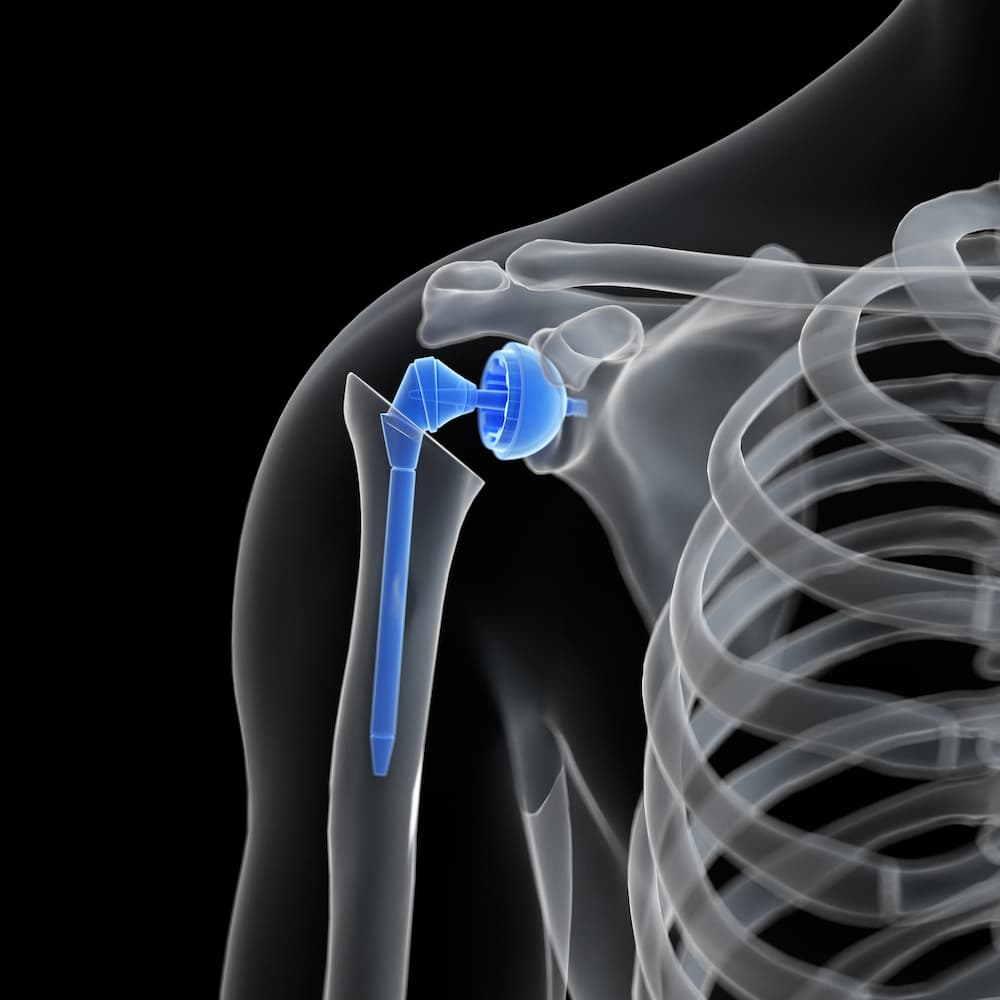

Joint Replacement Surgery

These pages are designed to give you the right information about some common joint replacement surgeries, along with some advice and exercises to help you with your rehabilitation.